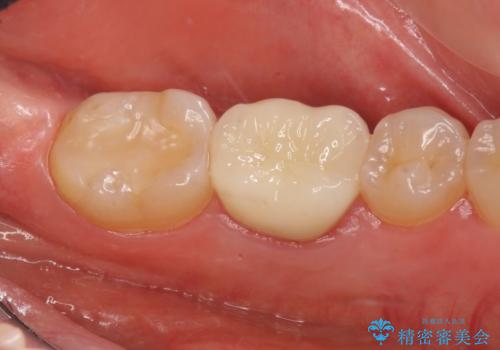

手術後、きちんとマージンラインが歯肉の上に来た状態で、セラミックインレー修復を行いました。

また、左下6番は専門医(銀座院院長 Dr.林)による再根管治療を行いました。

- 38万円(左下7:歯周外科処置5万円、セラミックインレー7万円 左下6:精密根管治療(再治療・専門医による)13万円、ファイバーコア2万円、ジルコニアクラウン10万円、仮歯1万円)費用は治療当時の料金となります